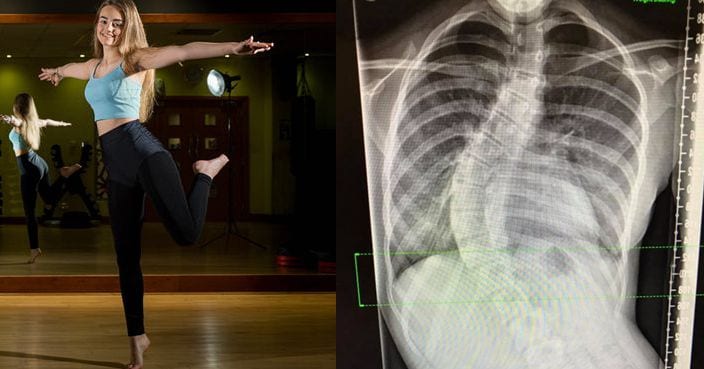

[post_page_title]70-degree curve[/post_page_title]

After her first consultation with a specialist, the curve was already noticeable in her spine, but by the time the vacation in Greece was over, it had worsened.

Lily joined her family in Greece in May 2017, and upon returning was scheduled to have her life-changing surgery in August. The curve was just too much now, and it was becoming so noticeable that Lily knew the time was right to trust the surgeons to do their thing.